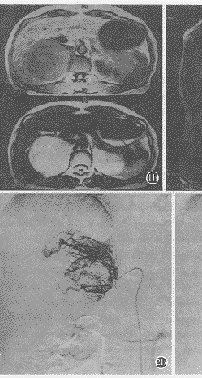

DSA表现:腹主动脉及选择性肾上腺动脉造影显示动脉期肾上腺血管分支增多、扩张、扭曲,以肾上腺中动脉造影时更明显,其中2例见少许静脉早显。实质期肿瘤染色浓密,欠均匀,静脉期仍见肿瘤淡薄染色。瘤体所波及的肝、胰、肾处未见其血管异常染色(图2)。

图2 与图1为同一患者。选择性腹腔动脉造影,显示肝动脉分布、形态正常,右膈下动脉发出的右肾上腺动脉远段增粗、扭曲(a)。选择性肾上腺中动脉造影动、静脉期,见大量增粗、增多、扭曲的肿瘤血管,动脉期见少许静脉早显,静脉期仍见瘤体染色浓密(b、c) 。

嗜铬细胞瘤富含血管,腹主动脉及肾上腺动脉造影示肾上腺动脉增粗,肿瘤血管多而密集,呈网状,迂曲走行,粗细不均,可见静脉早显,实质期有明显的肿瘤染色,静脉期仍见淡薄肿瘤染色。如伴坏死、囊变,密集的肿瘤血管中常出现少血管区,实质期见染色缺损,反映嗜铬细胞瘤非常富于血管性及延迟显影的特点[3,5,6]。一般以肾上腺中动脉血管增粗及肿瘤血管增多更为明显,可能与肾上腺中动脉和肾上腺上、下动脉之间存在广泛吻合有关。肿瘤所波及的邻近器官,未见其供血动脉增粗及肿瘤染色征象。本组6例造影表现典型,2例动脉期见少许静脉早显。